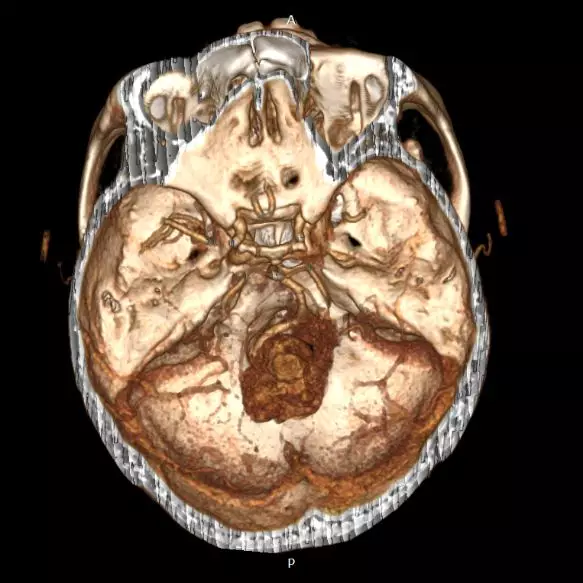

术前CTA同样提示肿瘤血供丰富